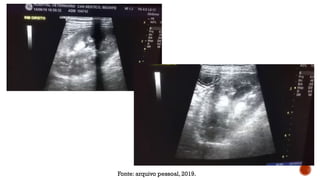

Fonte: arquivo pessoal, 2019.